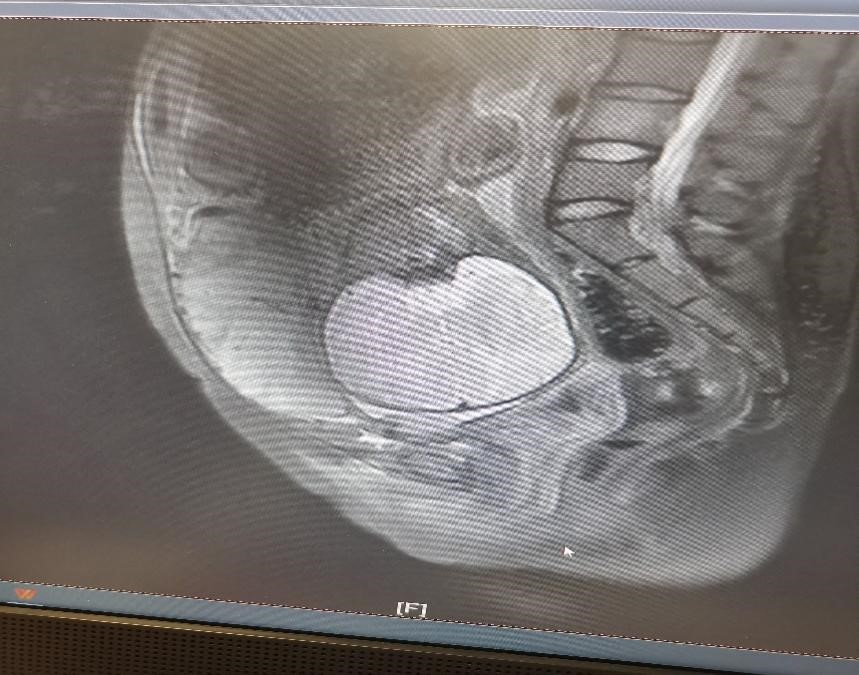

小彭在怀孕早期查B超就提示疤痕部位妊娠可能,医生向患者及家属告知相关风险,但患者及家属继续妊娠意愿强烈。孕14周胎盘完全形成,结合B超结果(胎盘附着在子宫前壁等)和前次剖宫产病史,判断为凶险性前置胎盘(图1)。此时小彭面临困境在于无论是选择终止妊娠还是继续妊娠,出血、切子宫的风险都很大,甚至有危及生命的可能:若选择终止妊娠,可能因出血切除子宫导致无法生育;若选择继续妊娠,分娩时面临的风险同样是大出血切子宫,但能保住孩子,最后经过患者及家属商量后,决定承担风险,继续妊娠。

图1

小彭在孕32+5周时,外院磁共振检查却提示未见胎盘植入,但B超始终提示胎盘内见数个液性回声,前壁峡部肌层内血流信号丰富,磁共振与超声的检查结果似乎不一致,患者及家属辗转苏州多家医院咨询相关风险,一路奔波,最后来到我院找到妇产科张跃明主任。张主任仔细阅读磁共振片子(图2),发现胎盘虽未完全覆盖宫颈内口,但整个胎盘位于子宫下段前壁及前次剖宫产疤痕处,子宫下段前壁肌层缺如,认为此例凶险性前置胎盘情况不可小觑。随后通过B超检查行胎盘植入评分为5分(≤5分为轻度),如果按胎盘植入分判断,可期待至37周终止妊娠即可,所需输血量较少,且无需其他学科参加。但张跃明主任凭借多年丰富的临床经验,结合磁共振图像及B超评价,认为情况远不如看上去一般轻松。目前产妇已孕36+4周,不能继续再期待,应立即收入院。

图2